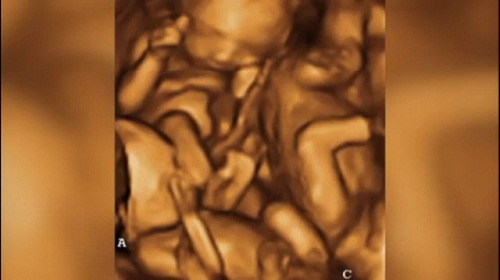

Chiếc bụng của cô bé tuổi teen lớn lên từng ngày, kết quả siêu âm với ba bào thai đang phát triển rất tốt khiến cho gia đình vui mừng và không nghi ngờ gì.

Tuy nhiên, sự thật sau đó ngày càng được hé lộ khi cô gái mang thai đến tháng thứ 10 mà vẫn chưa sinh. Cùng lúc ấy, một thành viên của nhóm “Moms of Triplets” phát hiện điều bất thường trong hình ảnh siêu âm mà cô gái đã đăng trên mạng.

Cuối cùng sự thật đã được hé lộ. Hóa ra tất cả những ảnh siêu âm cô gái đưa lên đều là giả, ngay cả cái bụng bầu cũng là đồ giả và được cô gái tìm mua trên trang mạng.

| Hình ảnh siêu âm giả |